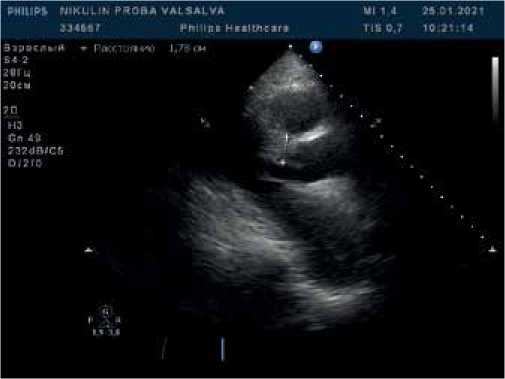

Рис. 3. В-режим + CW-режим. Апикальная 5-камерная позиция. Исследование кровотока в ВТЛЖ при поведении пробы Вальсальвы. Прирост систолического градиента, максимальный систолический градиент 82,8 мм рт.ст.